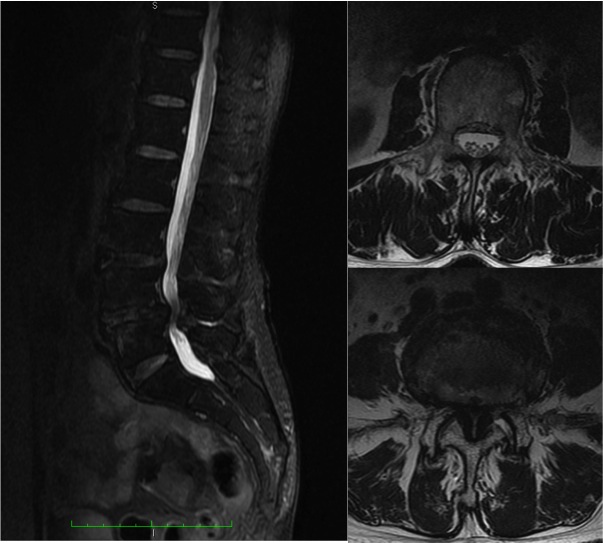

■從磁力共振中可見腰第四、五椎管嚴重狹窄。右上圖:正常的腰椎管寬度,右下圖:腰第四、五椎管的神經組織幾乎看不見了。